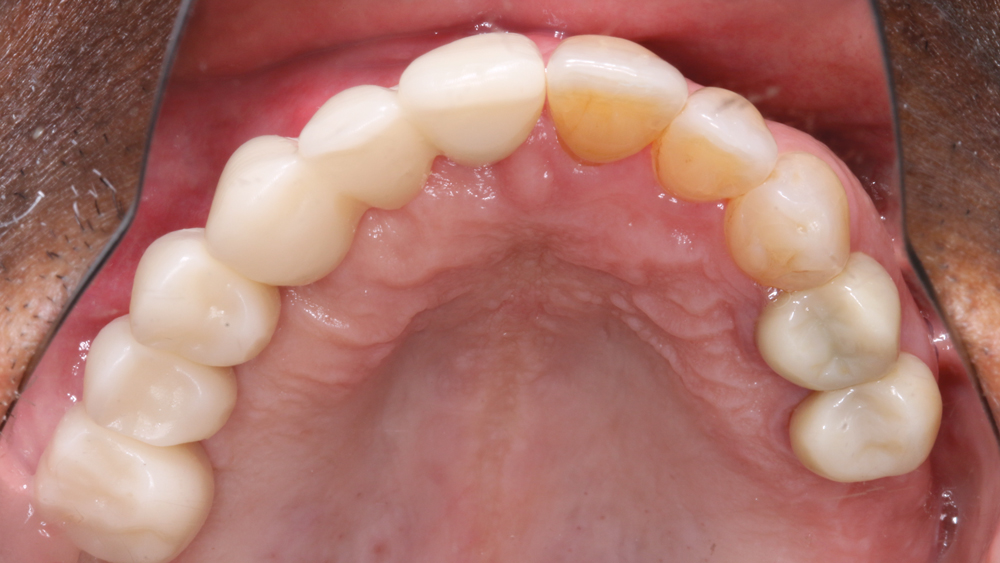

RESTORATIVE TECHNIQUES FOR ESTHETICS AND OCCLUSION

Esthetics and occlusion can be challenging in these types of cases. Restoring half an arch and trying to mirror the contralateral soft tissue and dentition with proper contours and shade requires patience and resolve. The lab provided a PMMA try-in prosthesis, which I evaluated with Weldon. The try-in allowed us to easily resolve any discrepancies with the prosthetic design and develop ideal occlusion. Once Weldon agreed on the esthetics, the PMMA provisional was returned to the lab and duplicated in BruxZir Solid Zirconia. This extra step eliminates excessive chairside adjustments upon seating of the final prosthesis.

The PMMA try-in prosthesis ... allowed any necessary adjustments to easily be made to the prosthetic design prior to milling the final BruxZir restoration.

BruxZir Solid Zirconia has proven to be extremely strong yet compatible with opposing natural dentition; the material exhibits minimal wear on the opposing enamel. Its color and shading are extremely natural in appearance, and I have no concerns about chipping or cracking of the material over time. The final seating of the prosthesis was straightforward, and I have confidence that the material is a long-lasting solution. Weldon was thrilled with the final restoration, as we were able to surpass his expectations and provide him with a fixed, functional, esthetic result.